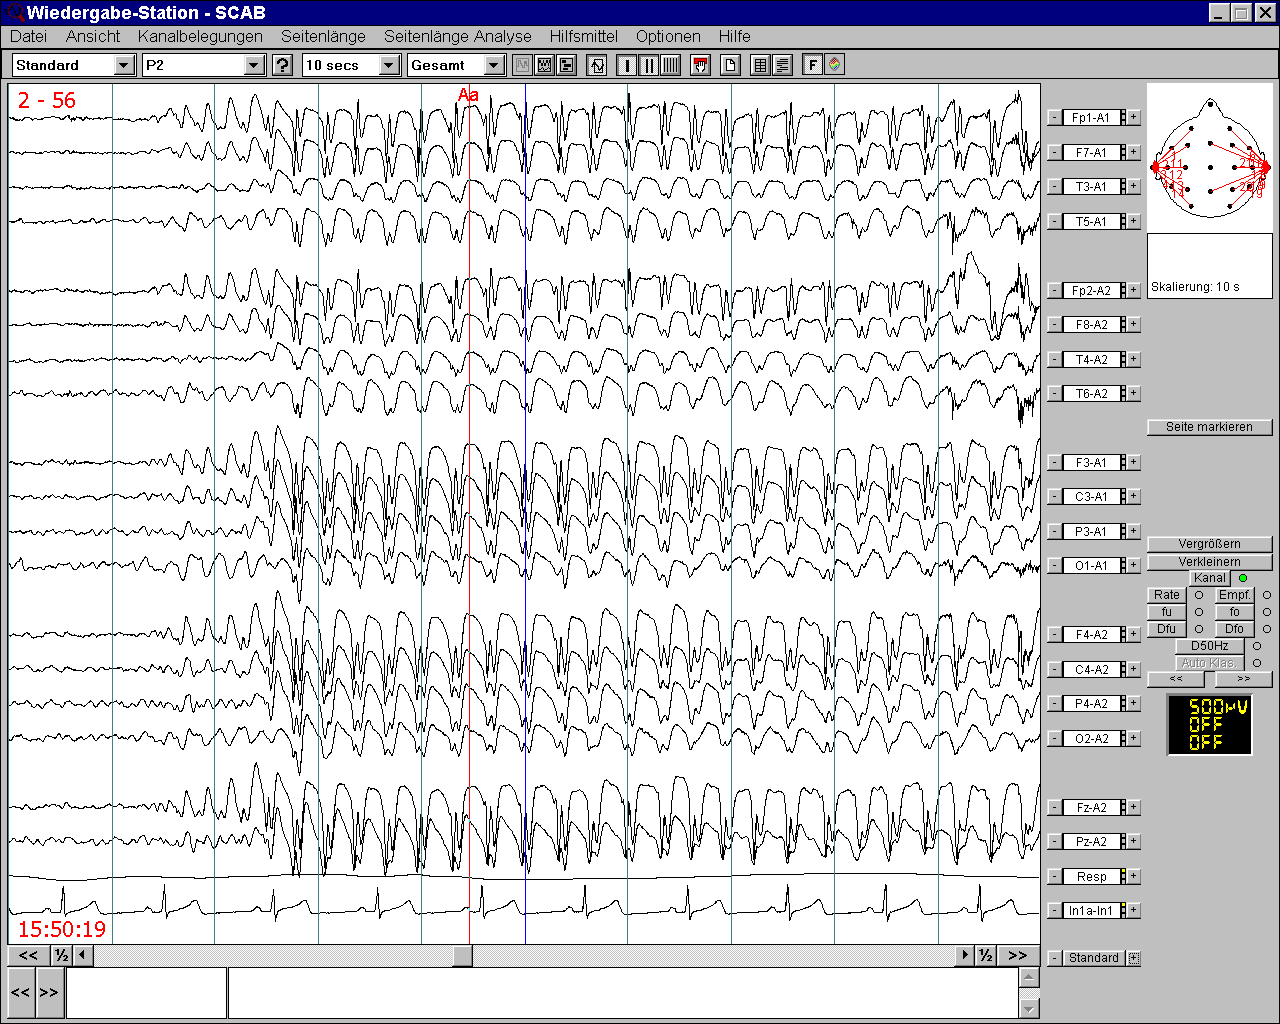

EEG

Bei der Elektroenzephalographie (EEG) werden Ihre Gehirnströme aufgezeichnet. Hierbei können epilepsietypische Veränderungen aufgezeichnet und bestimmten Hirnregionen zugeordnet werden.

epileptischer Anfall (Absence) im EEG mit spike wave-Komplexen

Die Sensitivität des EEGs kann durch unterschiedliche Aktivierungsmethoden gesteigert werden. Hierzu gehören Hyperventilation (hierzu werden Sie während des EEGs gebeten, tief zu atmen), Fotostimulation (hierzu werden Ihnen während des EEGs Blitzlichter gezeigt) und Schlafentzug. Für ein Schlafentzugs-EEG werden Sie stationär für eine Nacht aufgenommen. In dieser Nacht sollten sie möglichst nicht schlafen. Das EEG wird dann am folgenden Morgen durchgeführt.